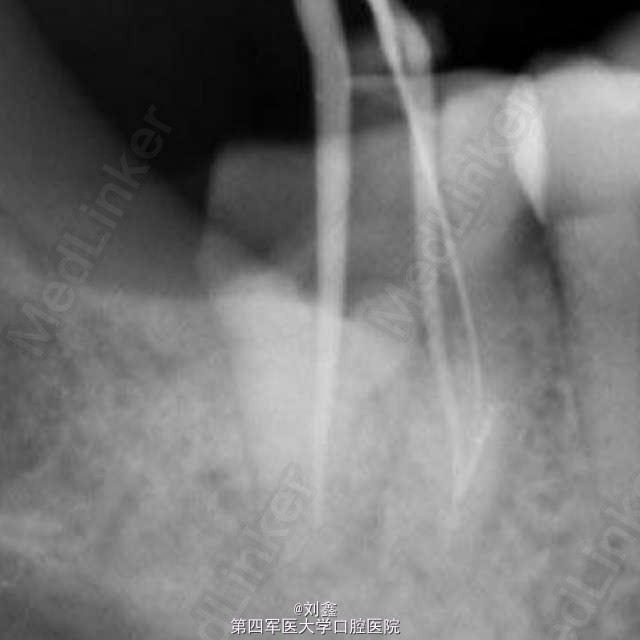

经典病例 根管内断针再治疗

患者女,29,右下后牙3年前于外院行治疗,冲填物脱落来我科。牙片示近中根有断针,遂行再治疗。

应用断针通过术治疗根管内器械分离